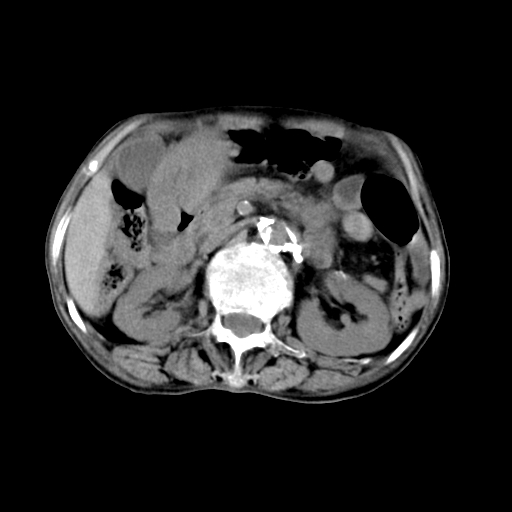

标题: CT19149:女,68岁,腹胀、恶心两周。 [打印本页]

女,68岁,腹胀、恶心两周,先做ct平扫,当时家属不同意强化,6天后家属要求增强扫描。

1)不排除胃窦癌;建议行胃镜检查。 2)局灶性脂肪肝。腹水。

考虑:胃窦ca,腹水,脂肪肝

1)胃窦壁厚,考虑胃窦癌?建议行胃镜检查。 2)局灶性脂肪肝。